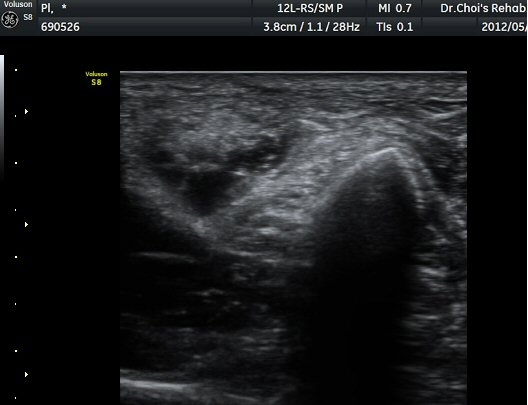

À­´Ù¸®(thigh) ¾Æ·¡ ºÎÀ§ ¿ÜÃø Ⱦ´Ü¸é°Ë»ç¿¡¼­ À̵ιڱ٠³»Ãø¿¡¼­ ÃѺñ°ñ½Å°æÀÌ Á¤»óÀûÀ¸·Î °üÂûµÈ´Ù(±×¸² 1, 2).